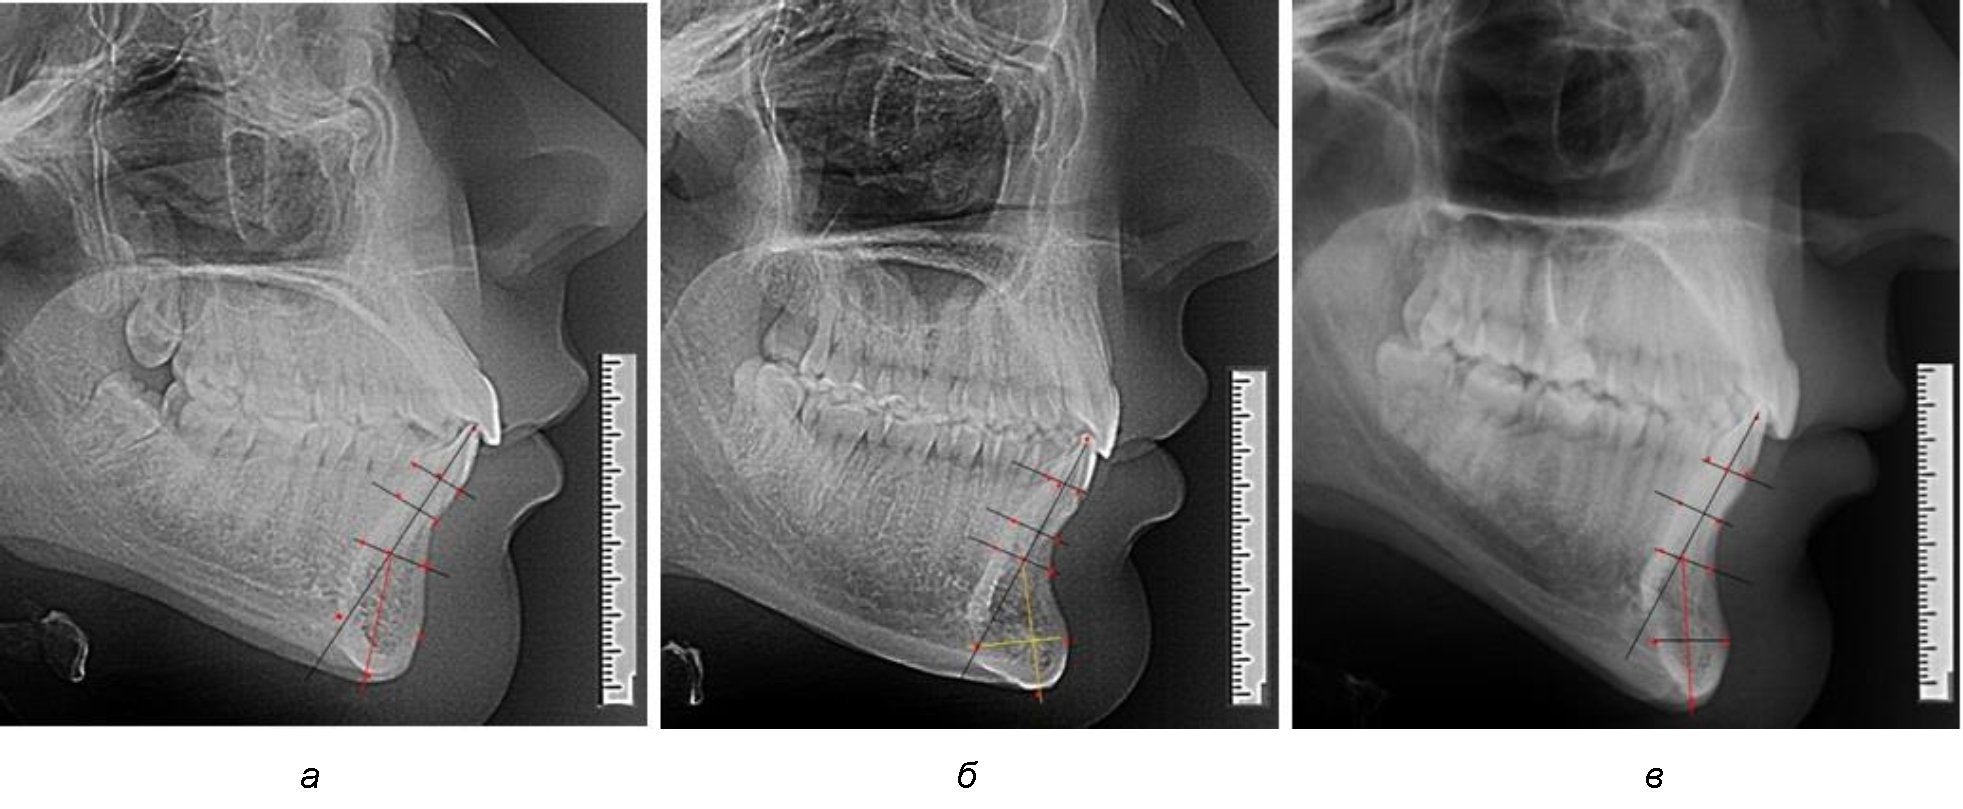

Варианты резцовых сегментов нижней челюсти различные как по ширине, так и по высоте, а также по расхождению положения апикальных точек по Downs и Schwarz представлены на рис. 4.

Рис. 4. Особенности нижнечелюстного резцового сегмента на ТРГ у людей при среднем (а), широком (б) и узком (в) вариантах

Нередко отмечается деформация подбородочного выступа и различное его положение по отношению к зубоальвеолярной части сегмента. При мезиальной окклюзии нередко нижняя подбородочная точка смещается кзади по отношению к условной срединной вертикали нижнего резца, а при дистальной окклюзии отмечается компенсаторное отклонение подбородка кпереди (рис. 5).

Рис. 5. Особенности нижнечелюстного резцового сегмента на ТРГ у людей при мезиальной (а) и дистальной (б) окклюзии

Кроме того, так же как и у людей с физиологической окклюзией, определялось различие в положении апикальных точек Downs и Schwarz, что, по нашему мнению, может определять тактику лечения патологических форм протрузии/ретрузии резцов с учетом биотипа костной ткани.